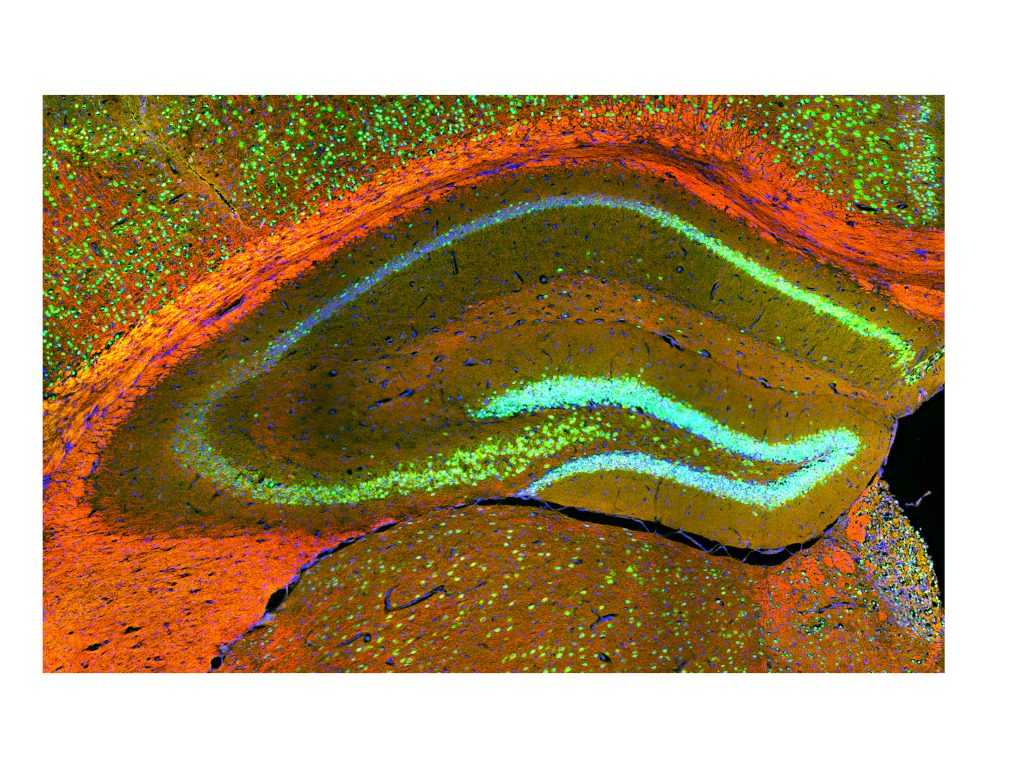

Anejos: fotos Expo “NeuroArte”: Una década revelando ciencia microscópica

Durante estos diez años, el CEN ha sido escenario de importantes avances en biología celular, neurociencia e investigación biomédica. Entre sus logros se destacan producir más de 140 publicaciones científicas en revistas revisadas por pares; la obtención de varios grants competitivos de fondos federales que han allegado millones para proyectos de investigación; apoyo directo a estudiantes graduados en el desarrollo de sus tesis de maestría y doctorado; contribución al desarrollo de patentes científicas por investigadores de la UPR; y la realización de talleres especializados y entrenamientos técnicos para cientos de participantes locales e internacionales.

El Centro de Excelencia Nikon (CEN), cuya casa es el Centro Molecular, desde su fundación ha sido un motor de innovación en microscopía avanzada, posicionando a Puerto Rico como un referente regional en bioimágenes. Esta instalación ha permitido el acceso a tecnología de punta para investigadores y estudiantes, fortaleciendo la capacidad científica local y conectando a la isla con redes internacionales de investigación.

El CEN se ha convertido en un semillero de talento científico, elevando las competencias de estudiantes subgraduados, graduados, postdoctorales y técnicos especializados. Su impacto va más allá del ámbito académico, al atraer proyectos colaborativos, alianzas con la industria biotecnológica y farmacéutica, y fomentar el desarrollo de startups y servicios especializados en la isla.